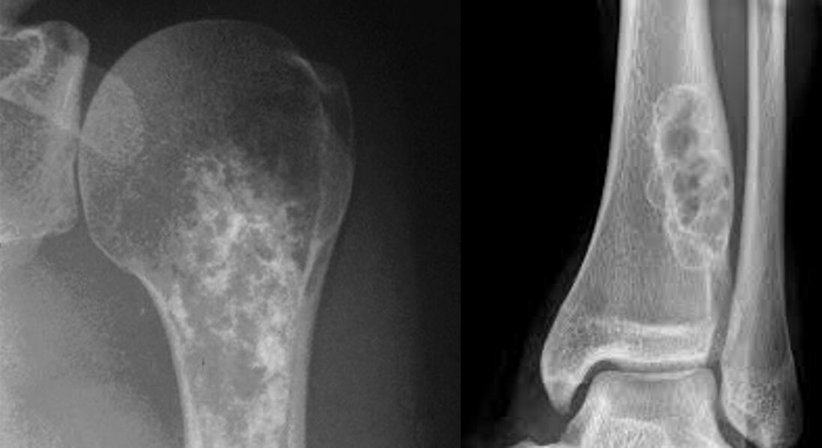

Knochen- und Weichteiltumore sind selten und können in gut- und bösartige Gewächse unterteilt werden. Eine frühzeitige, korrekte Diagnostik und Therapieplanung sind entscheidend für den Behandlungserfolg. Daher sollte bei Vorliegen eines Tumors des Bewegungsapparates ein Facharzt mit Spezialisierung in diesem Gebiet aufgesucht werden.

Kann ein Tumor nicht eindeutig anhand der Bildgebung zugeordnet werden, so wird eine Gewebeprobe (Biopsie) zur Sicherung der Diagnose notwendig.

Bei gutartigen Tumoren ist die Observanz möglich oder die gewebeschonende Entfernung (Resektion). Bösartige Tumore müssen immer vollständig, mit notwendigem Sicherheitsabstand, operativ entfernt werden. Die Prognose ist abhängig von der Art und dem Differenzierungsgrad des Tumors. Ebenso ist die interdisziplinäre Behandlung mit anderen onkologisch tätigen Abteilungen (Onkologie, Strahlentherapie, Pathologie etc.) unabdingbar.